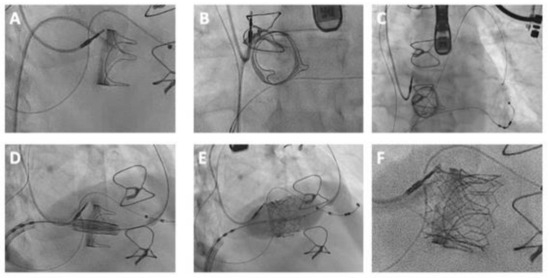

Navigating the tricuspid valve can be challenging, especially with a small valve orifice or severely dilated right atrium. Adjusting fluoroscopy helps provide an optimal view of the prosthesis, facilitating catheter guidance (Figure 6). Employing a multipurpose catheter with a shaped wire aids in directing the catheter toward the tricuspid valve. Additionally, using a steerable sheath in combination with an angled wire ensures a secure catheter position during guidewire deployment into the right ventricular apex [73,94,95].

Figure 6.

TAVI for treatment of a degenerated 25 mm Carpentier-Edwards bioprosthetic valve implanted in the tricuspid position. (A,B) Valve crossed with an Amplatz Left catheter and straight-tipped 0.035″ wire, which was (C) positioned in the pulmonary artery. (D,E) Implantation of a 26 mm Edwards Sapien S3 Ultra valve with (F) good final result on angiography.

5.3.3. Wire Positioning

Upon successful traversal of the tricuspid valve, the wire is most commonly positioned in the pulmonary artery for extra support, but right ventricular apical positioning is also possible (Figure 6).